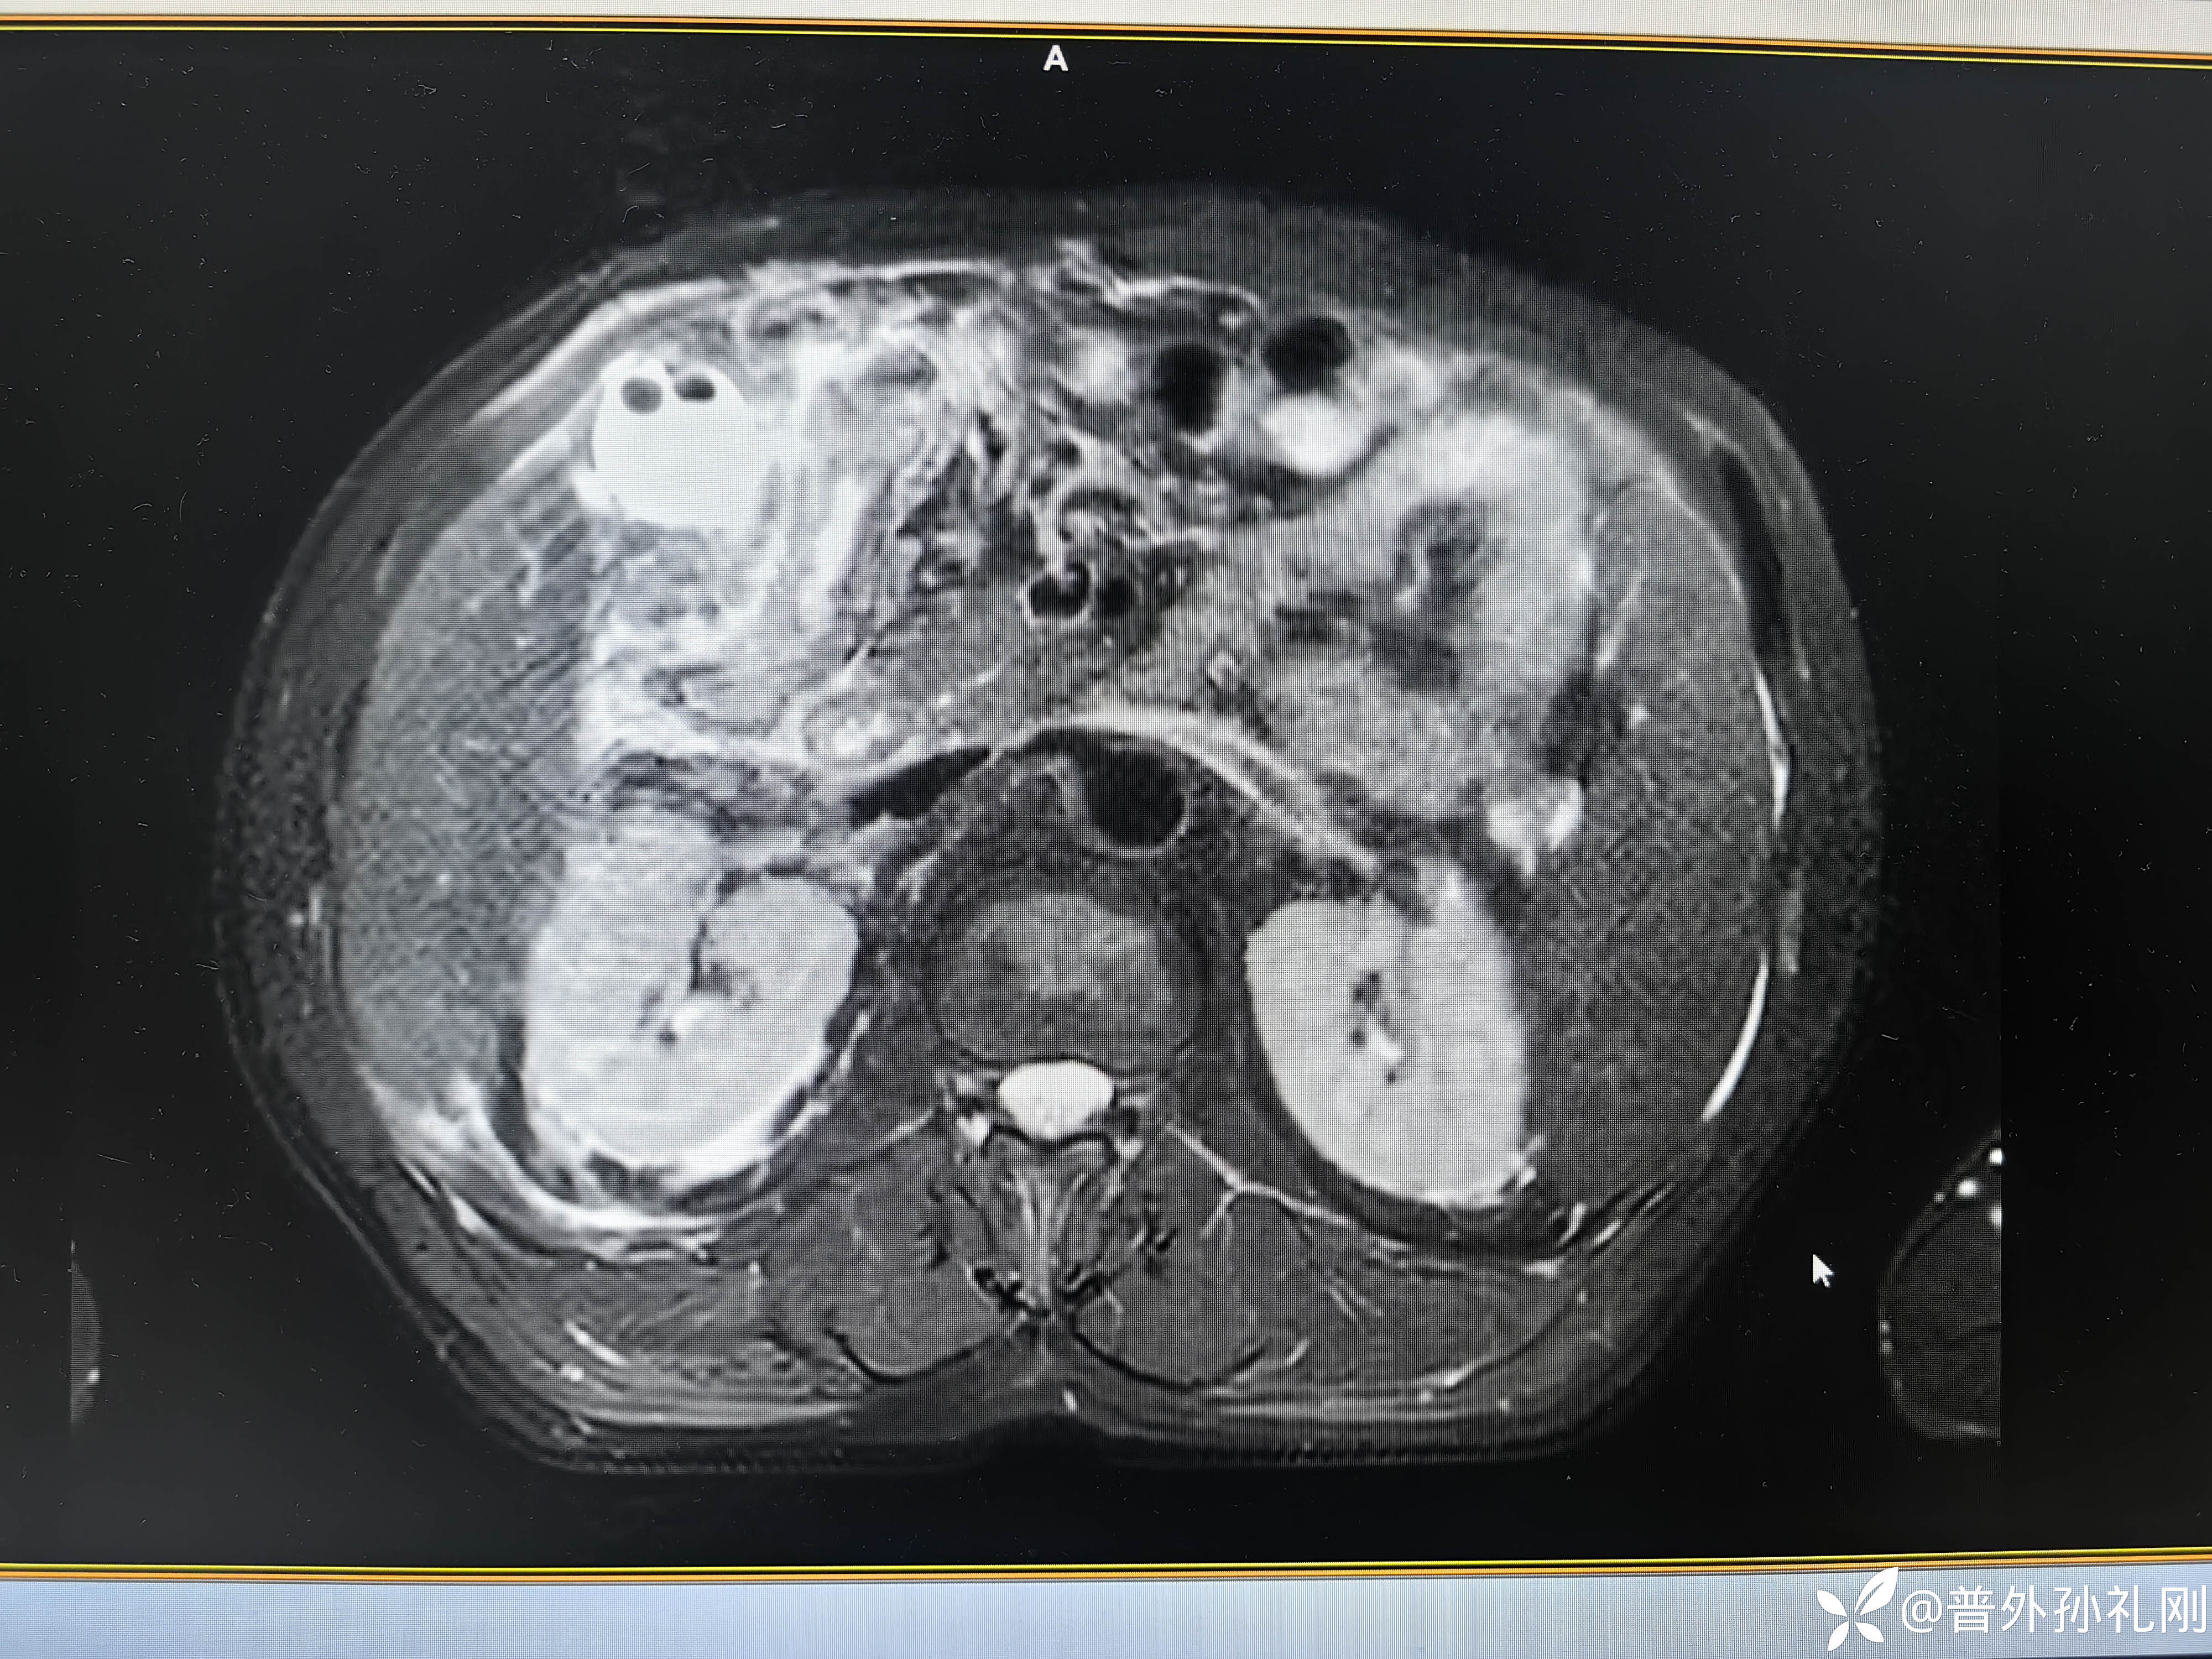

患者入院后积极完善相关检查,同时给予解痉、止痛、补液、抗感染等相关治疗,当晚患者腹痛逐渐缓解,午夜后能够渐渐入睡。由于患者病情重,入院后立即联系影像科安排次日上午(7月29日)急诊MRCP检查(按普通病人排队就不知道得等待几天了),次日上午行磁共振检查,结果如下:

胆囊周围白茫茫一片,而且靠近胆囊底部的腹壁都已经有明显的炎症水肿带了,还可以看到多发的胆囊结石,概括起来就是:胆囊及其周围组织均有广泛而明显的组织水肿、炎症渗出